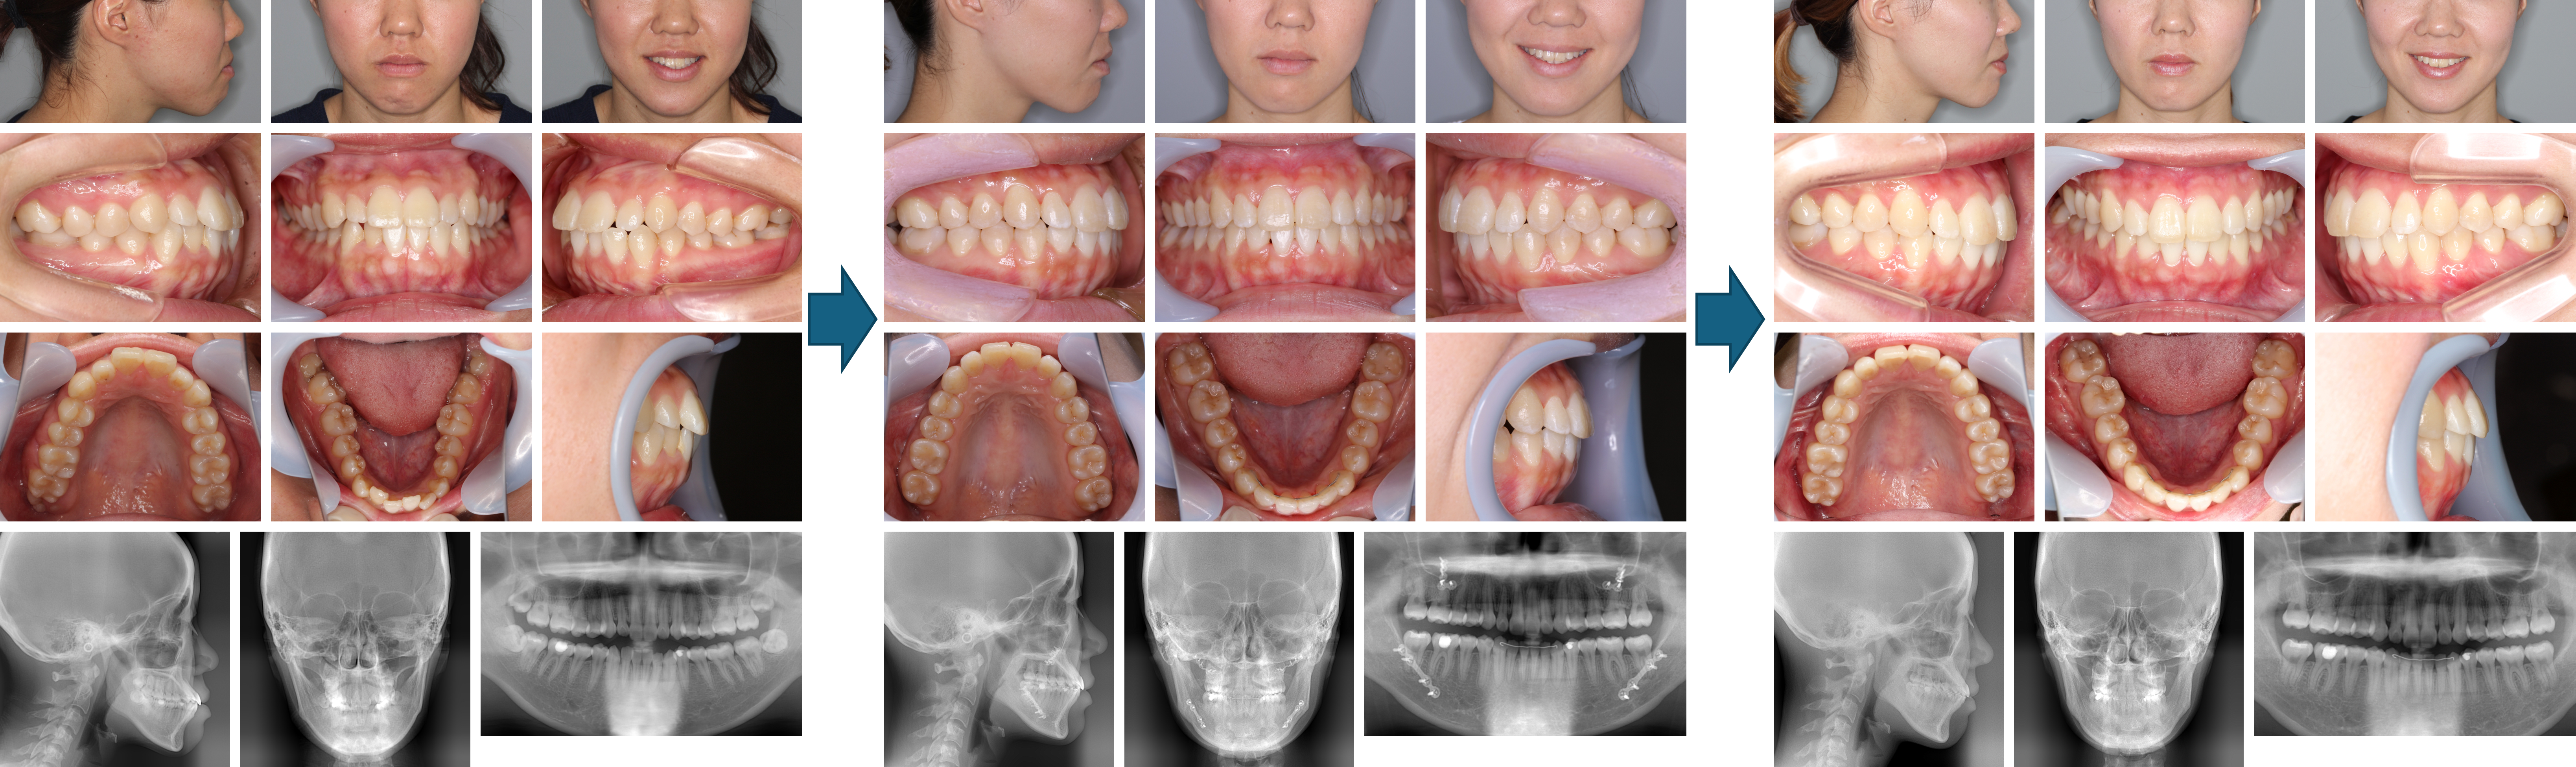

【治療例】初診時年齢:35歳4か月 / 性別:女性 / 主訴:上前歯が出ている、顎が小さい、口が開きにくい

治療の概要:上の前歯の突出および開咬障害を主訴に来院された。下顎左側犬歯の埋伏や歯肉退縮が認められたほか、根管治療や補綴治療の処置が施されていた。上顎はクワドヘリックス装置、下顎はバイヘリックス装置にて歯列の拡大を行ったのち、下顎左側犬歯及び上顎両側第一小臼歯の抜歯後に上下マルチブラケット装置でレベリングを開始したのち、上下顎骨手術を行った症例である。

主訴:上前歯が出ている、顎が小さい、口が開きにくい

診断名:下顎左側犬歯の水平埋伏と重度の歯肉退縮を認める上下顎前突

使用した主な装置:クワドヘリックス、バイヘリックス、マルチブラケット装置、顎間ゴム

抜歯/非抜歯および抜歯部位:抜歯(上顎両側第一小臼歯、下顎左側犬歯)

治療期間:3年4か月

治療回数:65回